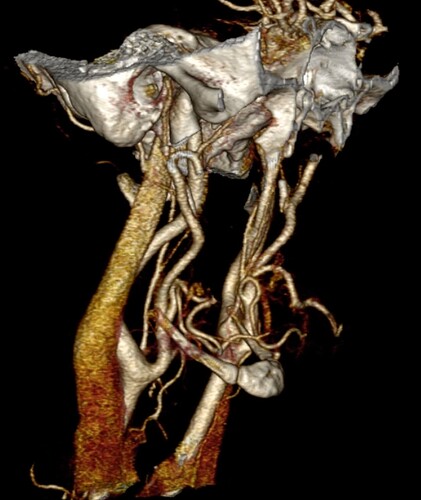

So, 2 years ago was the first time I came across Living with Eagle, filled with descriptions of all my symptoms, and a slew of scans showing very obvious bone chunks in the neck. Since I studied bio in college, and these bones are obvious, I figured I’d take a stab at looking at my own past scans and, low and behold, mild–but present–ossification of my stylohyoid ligament. Perhaps more relevant in my case, in the process of learning enough of the anatomy to understand axial images I noticed another weird thing–my right external carotid artery is in the wrong place. Instead of sitting lateral to my hyoid greater cornu, it’s medial. Hmm.

Tonsil surgery did solve the problem of my tonsils hurting, because they were gone, but no resolution of other symptoms. This was a year ago. I’ve been to PT, SLP, and now back to PT while I trial gabapentin for the neurologist. PT#2 discovered a bunch of significant atrophy in my upper right shoulder/back, and, you guessed it it’s all right sided. I’ve since then, thanks to radiopedia and Netter’s, also explored my images and noticed a few other anomalies in my scans, including an extended right thyroid superior cornu which appears to be pressing strongly into my neck also in the general area of pain, and an occipital artery branching off and wrapping around the internal carotid. Frustratingly these also weren’t mentioned on rads reports. My swallow study by the SLP showed obvious asymmetry with my swallow, but the SLP reported it symmetric and radiology apparently doesnt read the A/P view in their modified barium swallow studies? This is not inspiring faith in the academic institution I attended, but what can I possibly know they dont?

I’m here cause I’ve learned so much, and ya’ll seem to be the internet experts of weird head/neck issues adjacent to the stylohyoid chain. The docs keep seeing me, and keep ordering imaging, and seem to not be talking to each other at all? Frankly it seems to me the answers are in already in the images… so I’ve included several, perhaps you’ll see something helpful and can offer a suggestion… I just know I’m exhausted, frustrated, in so much pain all the time I cannot function which is so demoralizing, and it’s getting worse despite physician recommendations.